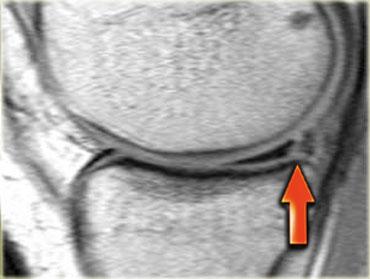

Chúng ta bắt đầu với lát cắt ở giữa của khảo sát.

Lưu ý thân sụn chêm bên có kích thước nhỏ với hình dạng bất thường (mũi tên xanh).

Phần bờ trong bị khuyết được nhìn thấy ngay phía ngoài dây chằng chéo trước (mũi tên đỏ). - Phần sụn chêm bị rách di lệch vào trong, tức là phần quai xách, có thể được theo dõi theo hướng ra sau trong hố gian lồi cầu.

- Tiếp tục.

- Đây là điểm nối giữa phần quai xách và sừng sau.

- Đây là lát cắt phía trước cho thấy một nang sụn chêm.

- Lưu ý tín hiệu cao theo chiều ngang.

- Tại đây chúng ta có thể nhận thấy sự phức tạp của tổn thương rách sụn chêm với thành phần theo chiều dọc và chiều ngang (các mũi tên).

Rách kiểu quai xách là loại rách dọc theo chiều đứng có kèm di lệch.

Mảnh bờ trong bị di lệch có hình dạng giống như quai của một chiếc xô.

Phần ngoại vi còn lại của sụn chêm, phần lớn hơn, có hình dạng giống như thân chiếc xô.

Loại rách này chiếm khoảng 10% trong tổng số các trường hợp rách sụn chêm.

Dấu hiệu PCL đôi

Dấu hiệu dây chằng chéo sau (PCL) đôi là một dải giảm tín hiệu nằm song song và ở phía trước-dưới so với PCL trên ảnh MRI mặt phẳng đứng dọc.

Đây là dấu hiệu có độ đặc hiệu cao trong chẩn đoán rách sụn chêm kiểu quai xô (3).